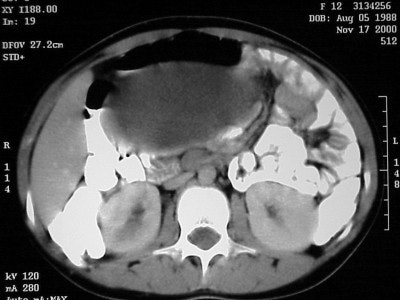

Axial images (Figures CT 10 and CT 11) show a mass beginning just below the kidneys on the left side and extending almost through the pelvis. The child was diagnosed with Wilm’s tumor of the left kidney.

![]() |

| Figure CT 10 |